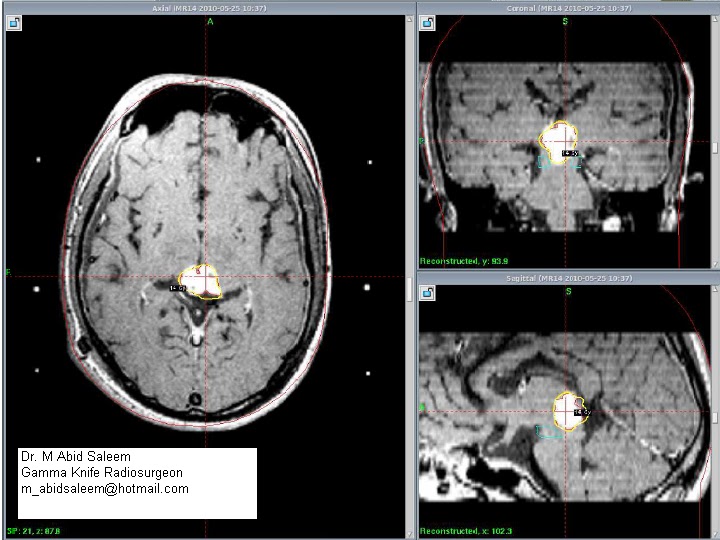

MR imaging showed an enhancing mass in the pineal region and obstructive hydrocephalus.MR Specrtroscopy revealed alow NAA and high choline.

V.P shunt was placed and he was treated with Gamma Knife.It was a single day treatment as usual and patient was discharged next day.